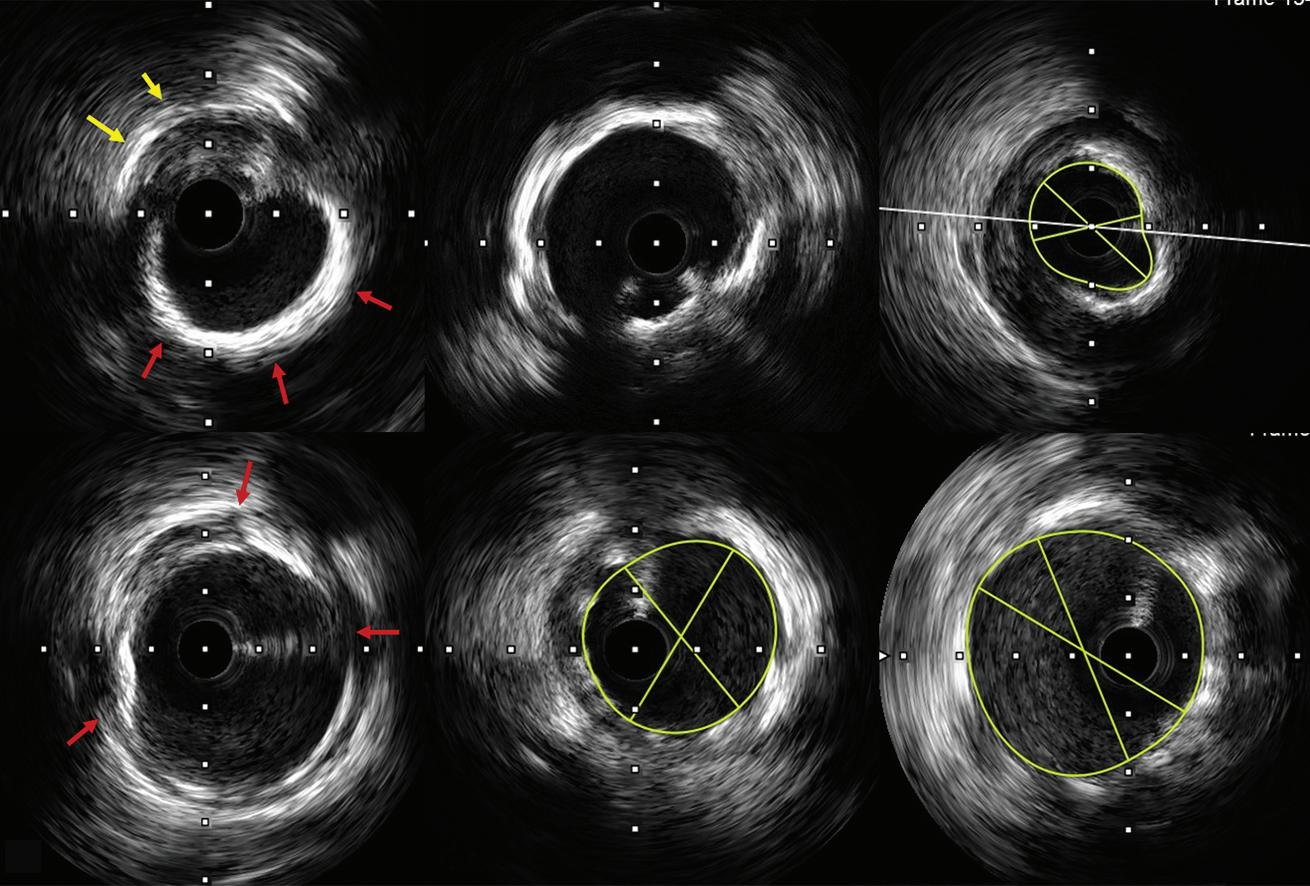

Hs-cTnT 12–52 ng/l and delta 3 to <5 ng/l at 1–3 h

Hs-cTnT >sex-specific 99th percentile or high risk score and 2–3 h delta >RCV

Hs-cTnT <sex-specific 99th percentile and low risk score

Not applicable

0/1 and 0/3 h 0/1, 0/2 and 0/3 h 0/2 and 0/3 h

Recommends the use of HEART risk score

Recommends the use of GRACE risk score models for estimating prognosis

Requires the use of HEART score for final disposition

Hs-cTn used Hs-cTnT Hs-cTnT and TnI Hs-cTnT and TnI

AMI = acute MI; APSC = Asian Pacific Society of Cardiology; ED = emergency department; ESC = European Society of Cardiology; GRACE = Global Registry of Acute Coronary Events; HEART = History, Electrocardiogram, Age, Risk factors and Troponin; Hs-cTn = high-sensitivity cardiac troponin; Hs-cTnT = high-sensitivity cardiac troponin T; RCV = reference change value; Malaysian = Malaysian Expert Consensus Group; TnI = Troponin I.